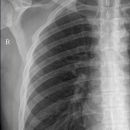

Hemithorax schräg

1.-7. Rippe: Inspiration, oberes Licht Prominenz

8.-12. Rippe: Exspiration, 1 QF oberhalb Beckenkamm

Die Rippen müssen vollständig abgebildet sein.